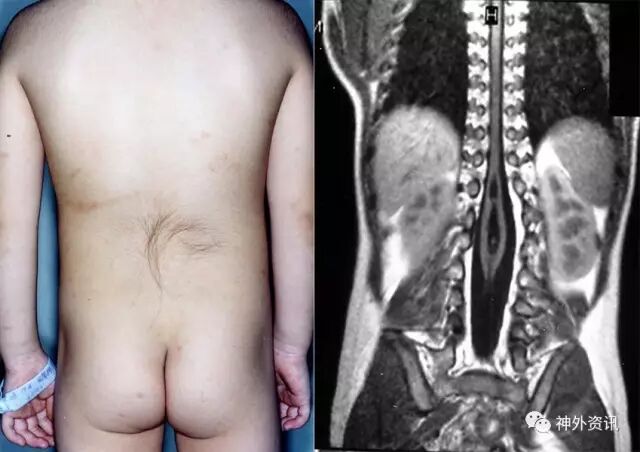

先天性神经管闭合不全

1.神经管闭合不全是新生儿期小儿神经外科常见的疾病之一

2.存活的新生儿约2%患先天性畸形。中枢神经系统相关的先天性畸形约64%与神经管闭合不全有关

脊髓纵裂

颅裂

分类

1.脑膜膨出

2.脑膨出

3.脑膜脑囊状膨出